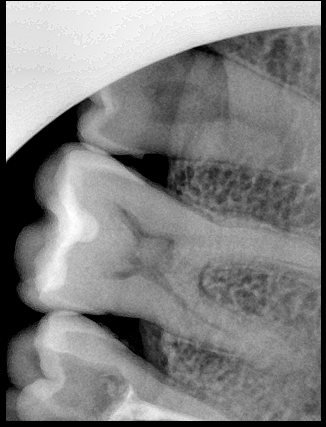

CR/DR 牙齿分割阶段记录

当前进展

- 完成了 CR/DR 牙齿相关分割训练

相关测试

遇到的问题

- 训练过程中出现过 mask 下移问题

- 部分结果会出现 box 填充异常

- mask 边缘仍然有比较明显的锯齿感

第三版算法分辨率效果比较

Updated: 2026-04-13(更新日期)

| 编号 | 原图 | 第一版 | 第二版 | 第三版 1216x1600 | 第三版 768x1024 | 第三版 1120x1120 |